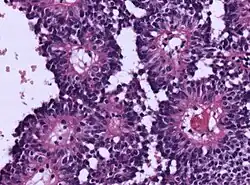

| Micrograph of an astroblastoma showing the characteristic nuclear pervivascular pseudorosette. H&E stain. | |

- Radial arrangement as a pseudorosette